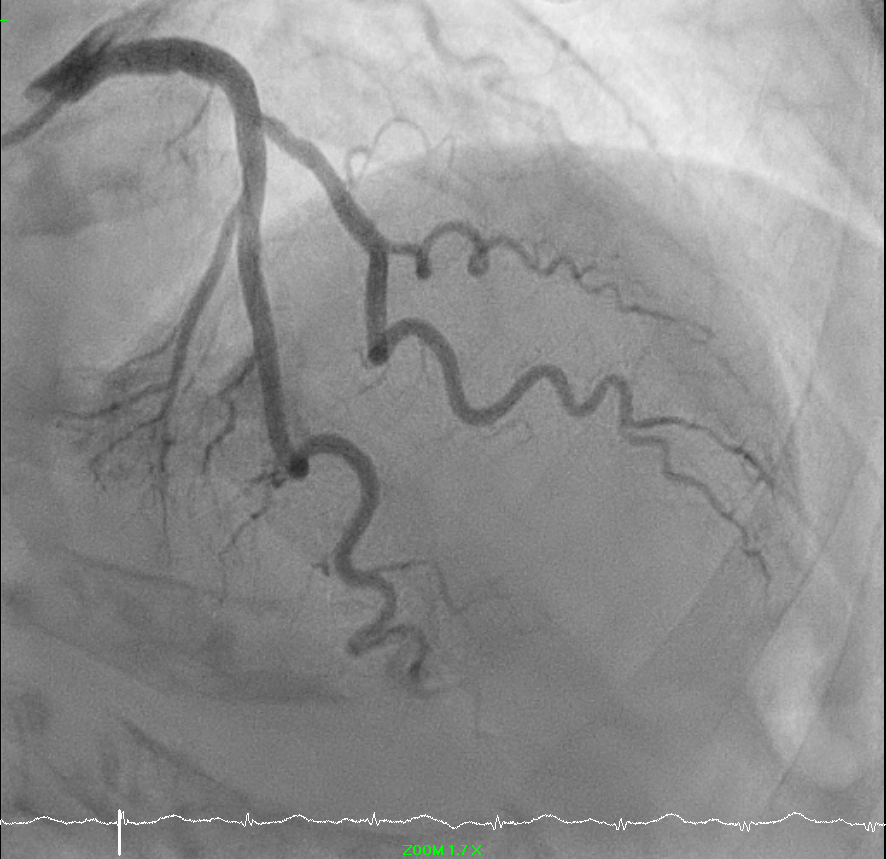

Coronary angiography showed complete total occlusion of right posterior left ventricular branch with collaterals from left system and moderate disease of first diagonal.

Right radial pulse was not strong. Ultrasound revealed a small right radial artery. Decided for left radial artery approach. Single puncture successful with ultrasound guidance. Optitorque 5FR catheter. Left coronary angiogram images obtained.